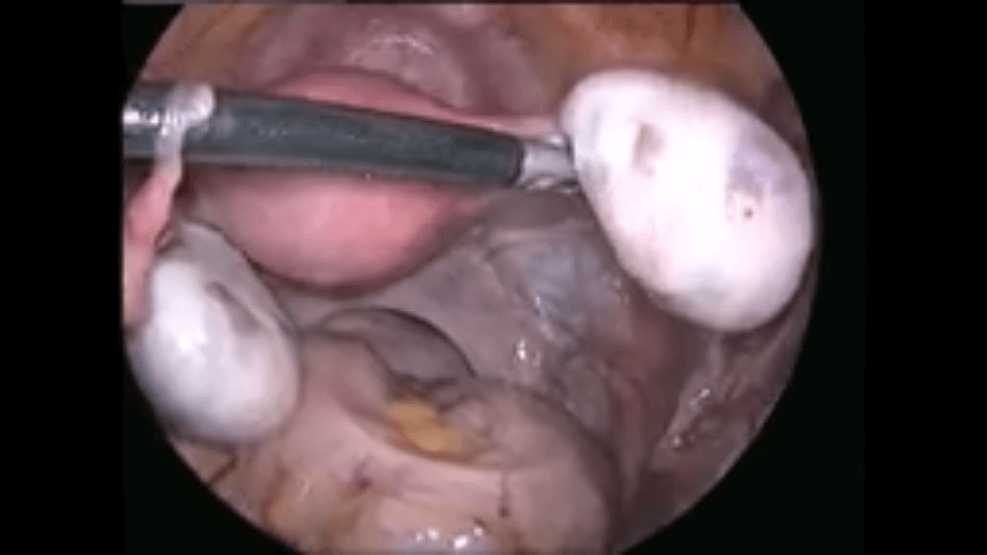

Laparoscopic Adhesiolysis and Ovarian Cystectomy